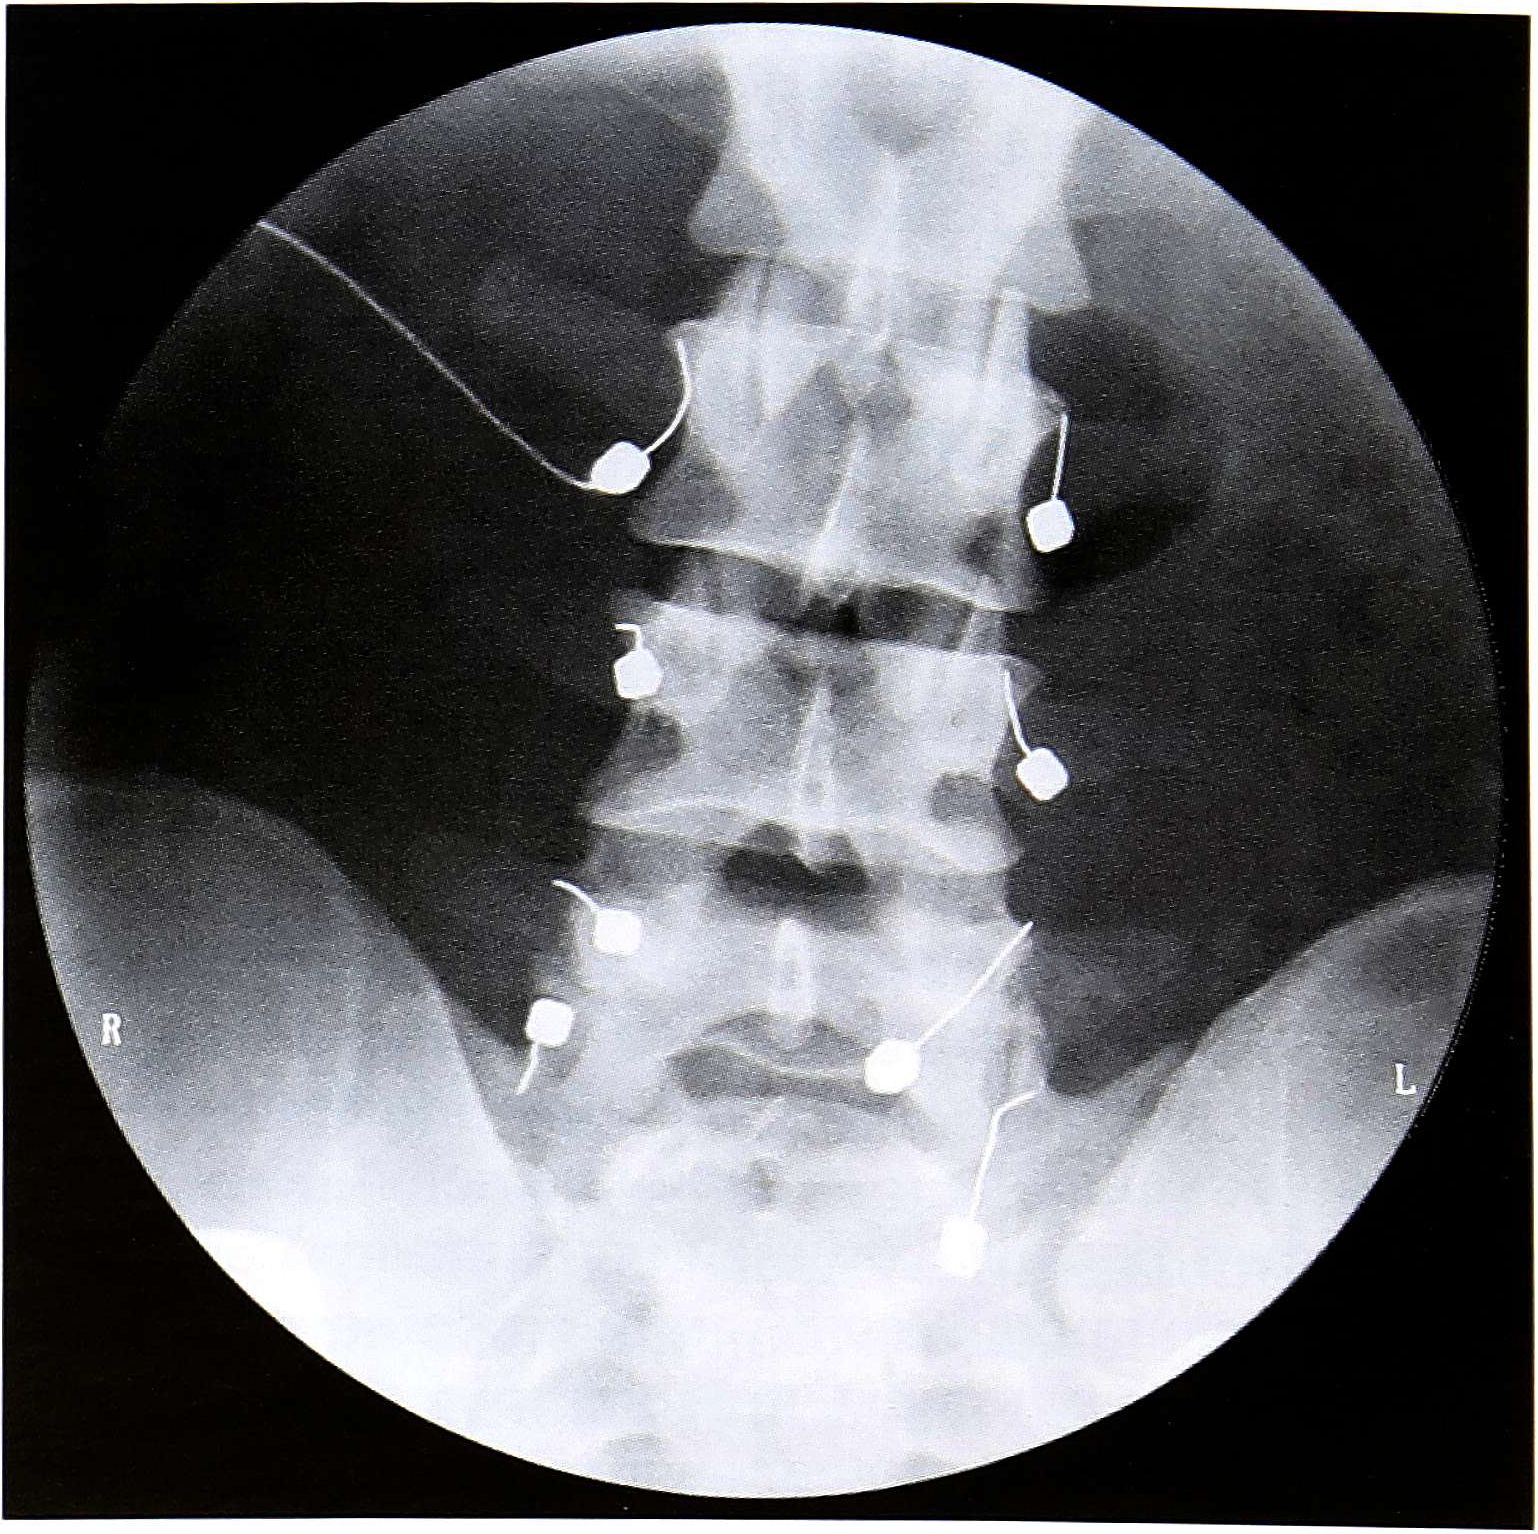

Больной К, 23 лет, мастер спорта по хоккею. После усиленных тренировок появились боли в поясничном отделе позвоночника. Неоднократно лечился консервативно (нестероидные противовоспалительные препараты, физиопроцедуры, мануальная терапия). В последнее время обострения участились, появилась иррадиация болей в правую ягодичную область. В отделении спортивной травмы ЦИТО по поводу синдрома фасеток поясничного отдела произведена чрескожная радиочастотная деструкция фасеточных нервов L2-3, L3-4, L4-5, L5-S1 с обеих сторон (рис. 3). Болевой синдром уменьшился сразу после операции. Выписан домой на следующий день. Через 2 нед приступил к тренировкам.

Рис. 3. Больной К. Рентгенограмма во время операции радиочастотной деструкции фасеточных нервов.